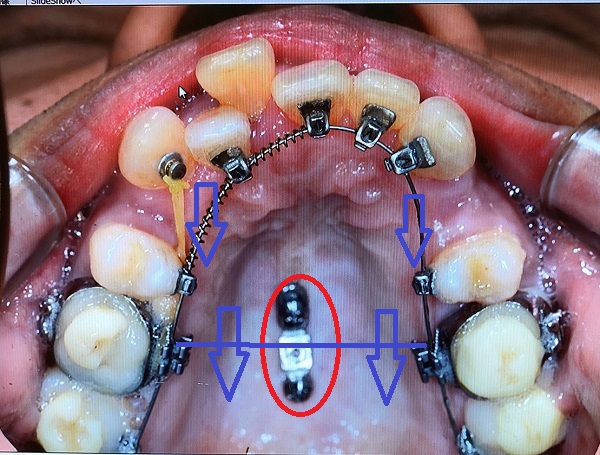

赤○内のインプラントから両側の奥から2番目を結束して固定(※画像では青い直線でつないだイメージにしています)すると、奥歯が前方向に動くことを抑制します。

アンカーインプラントのアンカーとは碇のことです。

インプラントが碇の役目をして動こうとする歯をとどめます。

そして、前歯側が後ろに下げられるスピードが速くなります。

私の場合、抜歯のすき間がふさがるスピードが速くなるのとあわせて、前歯のガタガタもなおり、綺麗なアーチ型ができるスピードが上がります。

<矯正インプラント装着時 2018/11/03>

※わずかずつですが、前歯のアーチが形成されつつあります。

次回、2018/11/27に口蓋のインプラントと両側奥歯をつなぐ予定です。

インプラントと奥歯をつなぐと矯正のスピードがあがるとのことなので非常に楽しみです。